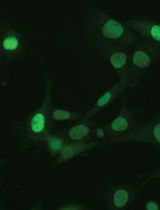

Figure 1. p-SMAD2 staining (arrowhead) in liver metastasis generated after intrasplenic injection of CRC cells. E: epithelial cells, Str: stromal cells. Scale bars = 10 μm